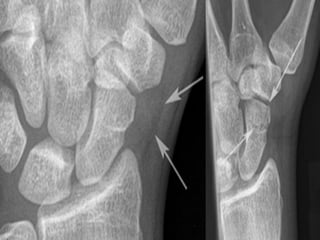

CT Scans

 CT permits accurate anatomic assessment of the fracture.

 Bone contusions are not evaluated with CT, but true fractures

can be excluded

Radiography  The 4essential views (ie, PA, lateral, supinated and pronated obliques) identify majority of fractures.  The scaphoid view is a PA radiograph with the wrist extended 30° and deviated ulnarly 20°. This view helps to stretch out the scaphoid and is also used for assessing the degree of scaphoid fracture angulation.  A clenched-fist radiograph has also been useful for visualization of the scaphoid waist.

CT Scans  CTpermits accurate anatomic assessment of the fracture.  Bone contusions are not evaluated with CT, but true fractures can be excluded